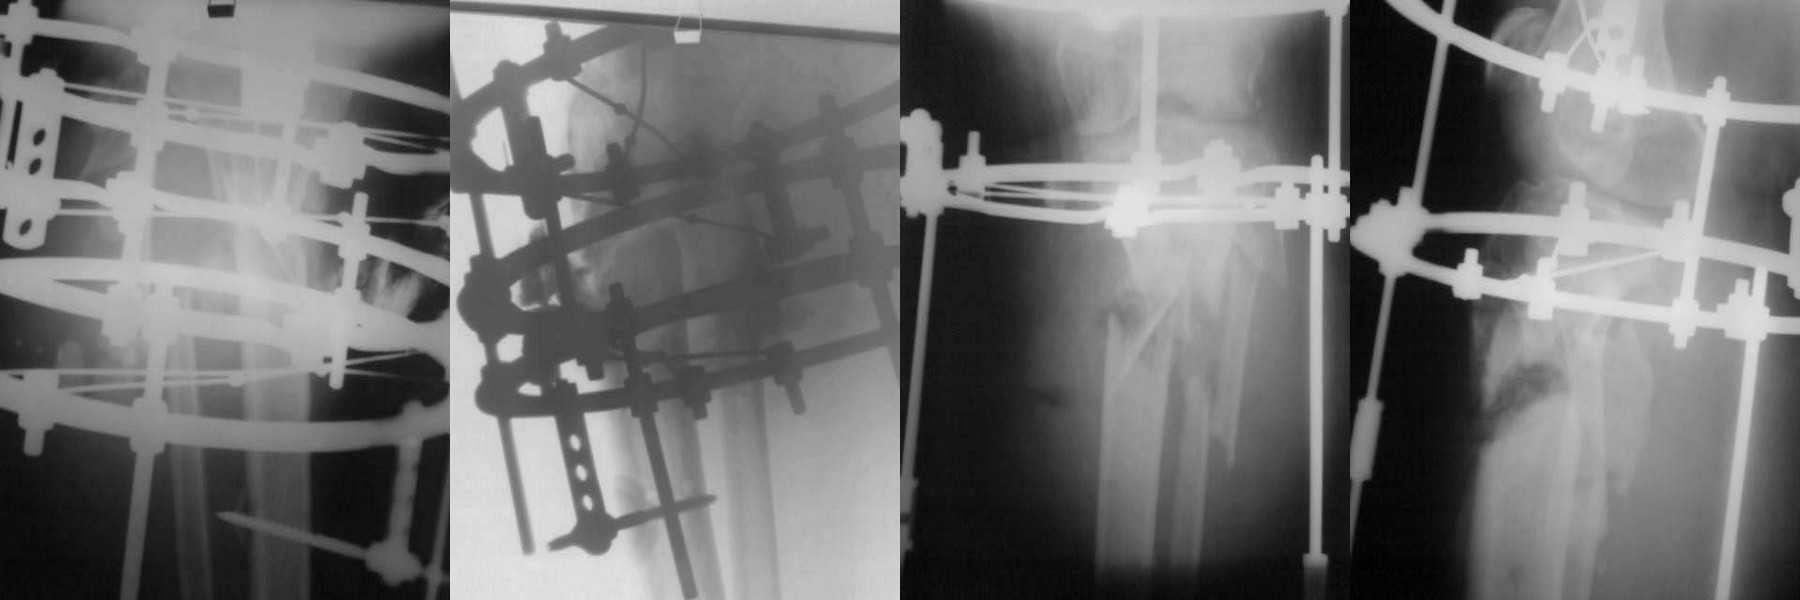

В данном случае используется подстопник с резинкой. досылаю результаты фистулографии, извиняюсь за качество рентгенограмм.